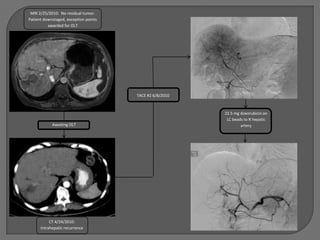

MRI 2/25/2010: No residual tumor.

Patient downstaged, exception points

awarded for OLT

TACE #2 6/8/2010

22.5 mg doxorubicin on

LC beads to R hepatic

Awaiting OLT                                          artery

CT 4/24/2010:

Intrahepatic recurrence